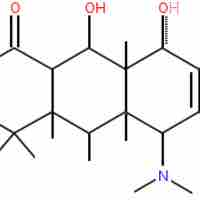

The β-lactam ring is part of the core structure of several antibiotic families.